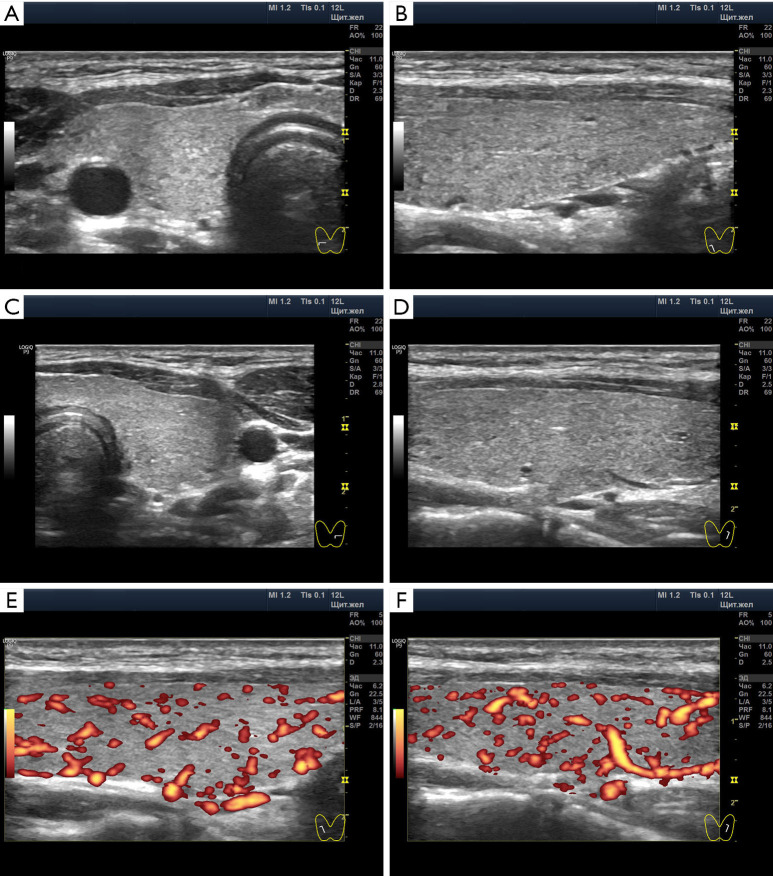

Case description: A 15-year-old female patient experienced a transition from SCH to euthyroidism against the background of highly normal values of thyroid hormones, the full state of the thyroid parenchyma and significantly increased blood flow in the Doppler mode. She did not take medications. Conditions likely to trigger SCH included acute respiratory illness, living in a cold climate, and mental stress due to prolonged preparation for exams. The transition to euthyroidism occurred after sufficient stay in the conditions of a southern resort in the summer and mental comfort.

Conclusions: As a result, it was revealed that the amount of thyroid-stimulating hormone (TSH) depends on the intensity of energy expenditure of the body in accordance with living conditions. The increased intensity of blood flow in the thyroid during SCH and euthyroidism shows the leading role of the autonomic nervous system and the auxiliary importance of TSH. The concentration of thyroid hormones at the maximum limit of normal in SCH, together with the significantly increased Doppler blood flow, suggests common elements of pathogenesis with Graves' disease through the autonomic nervous system. With many months of thyroid overstrain, ultrasound shows signs of corresponding depletion in the form of hypoechogenicity of the lobules, but the preservation of a sufficient amount of hormone-producing tissue.